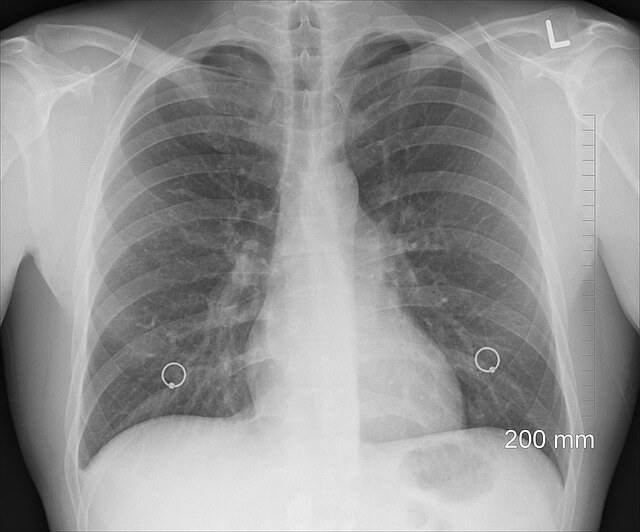

Najczęściej wykonywanym prześwietleniem jest rentgen klatki piersiowej. Ukazuje ono serce, tętnice, przepona, układ oddechowy w tym płuca i drogi oddechowe, a także szkielet klatki piersiowej i część kręgosłupa. Wykonuje się je wtedy kiedy mamy na przykład: trudności w oddychaniu, cierpimy na uciążliwy, chroniczny kaszel, duszności, choroby serca, odczuwamy ból w klatce piersiowej oraz gdy uległa ona jakimś urazom. Taki rentgen powinien być także profilaktycznie wykonywany co dwa lata, a w przypadku osób ze zwiększonym ryzykiem chorób płuc, raz na rok.